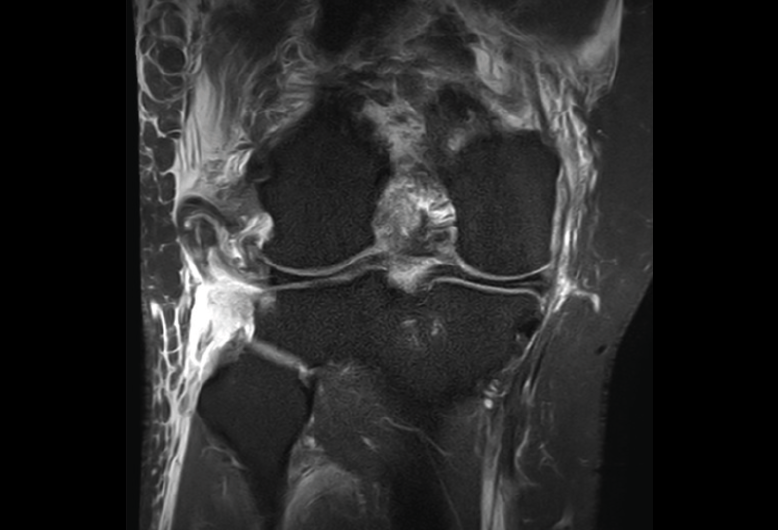

4.3. Osteocondritis

En la osteocondritis se aprecia una lesión subcondral caracterizada por resorción ósea, colapso y la formación de un secuestro.

El estudio por RM es una herramienta valiosa para diagnosticar e identificar las lesiones del cartílago. Conocer el aspecto del cartílago y saber cuánto y cuándo se lesiona, basándose en las clasificaciones actuales, permiten al radiólogo proporcionar la máxima información al clínico(20).

Figura 53. Corte de secuencia sagital (A) y axial (B) T2 Fat-Sat de RM de rodilla: lesiones osteocondrales en el fémur y la rótula.

Numerosos estudios demuestran la utilidad de la RM para definir la estabilidad o inestabilidad de la lesión en la osteocondritis, destacando su carácter no invasivo y la capacidad de valorar la progresión y la respuesta al tratamiento(21)(Figuras 53 y 54).

Figura 54. Corte de secuencia T1 y T2 Fat-Sat coronal de resonancia magnética: gran osteocondritis en el cóndilo femoral interno con edema en la medular adyacente.